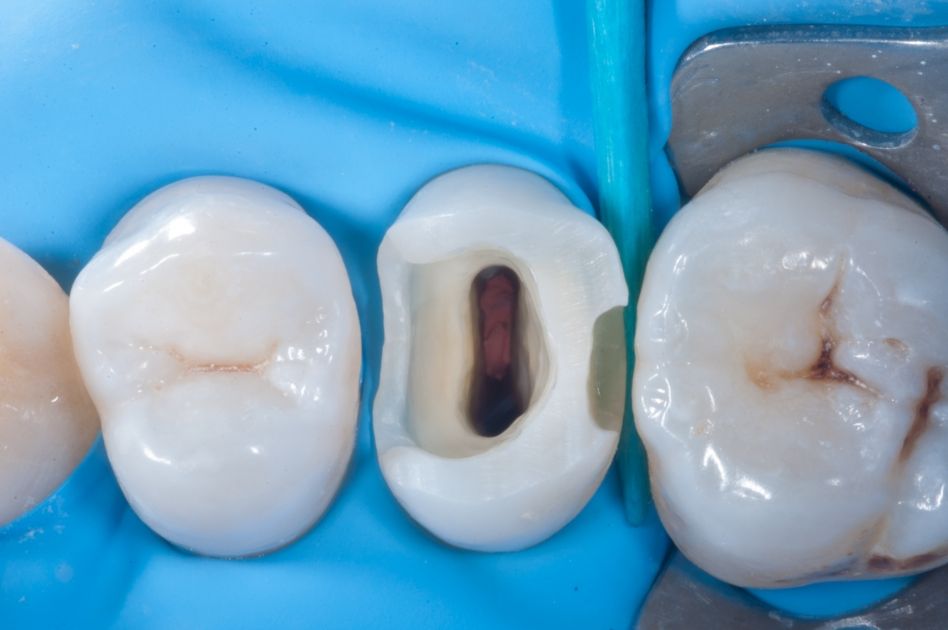

Рис. 1 Первоначальный вид окклюзионной поверхности.

Рис. 3 Изолируем рабочее поле коффердамом.

Рис. 4 Пульпа после удаления кариозного дентина.